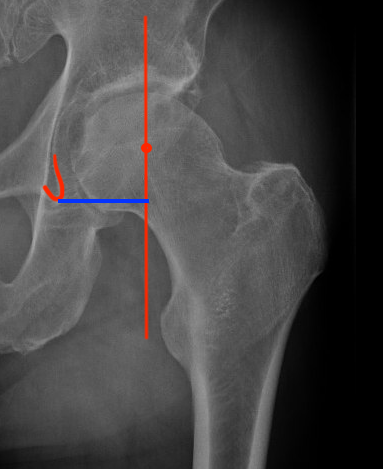

Acetabular offset

- perpendicular distance

- from the center of rotation of the femoral head

- to the vertical trans-teardrop line